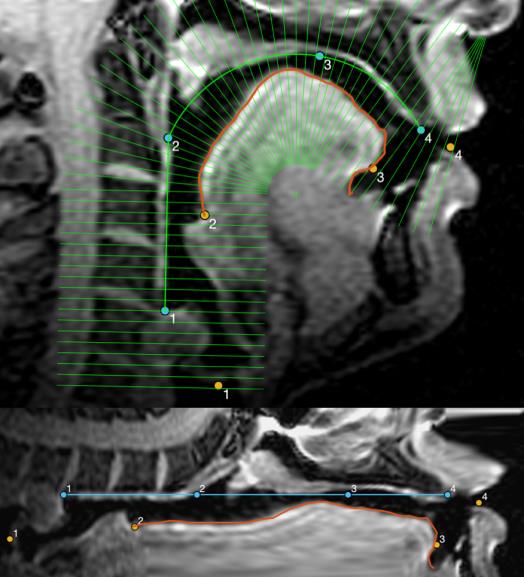

Real-time vocal tract MRI

Our lab is part of the Cornell Speech Imaging Group (SIG), a cross-disciplinary team of researchers using real-time magnetic resonance imaging to study the dynamics of speech articulation.

We will discuss this paper by Mark Tiede et. al: Production Allophones of North American English Liquids, where tongue data was collected by both MRI and Ultrasonic imaging.

The syllabic liquids [ɚ] (as in “purr”) and [əɫ] (as in “pull”) have well-defined acoustic targets but are produced with a wide range of heterogenous tongue postures.

This work surveys midsagittal tongue shapes from a large (N=78) number of speakers producing these sounds, to illustrate their variety, and to determine systematically how this variety can be quantified.

In particular we propose that a categorization based on just two parameters––degree of tongue dorsum convexity and tip orientation––is sufficient to classify observed shapes, and superior to defining ad hoc prototypes.